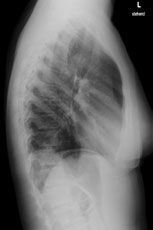

Radiologie Quiz 48

Eine 36-jährige Patientin kommt zu Ihnen in die Praxis. Sie berichtet über einen grippalen, fieberhaften Infekt, seit einer Woche bestehend.

In der Lungenauskultation sind Rasselgeräusche beidseits basal zu hören. Bei einem CRP von 160 mg/l veranlassen Sie ein Thoraxröntgen mit der Frage nach Infiltrat.

Hier sehen Sie die Bilder:

Wie lautet Ihre Diagnose?